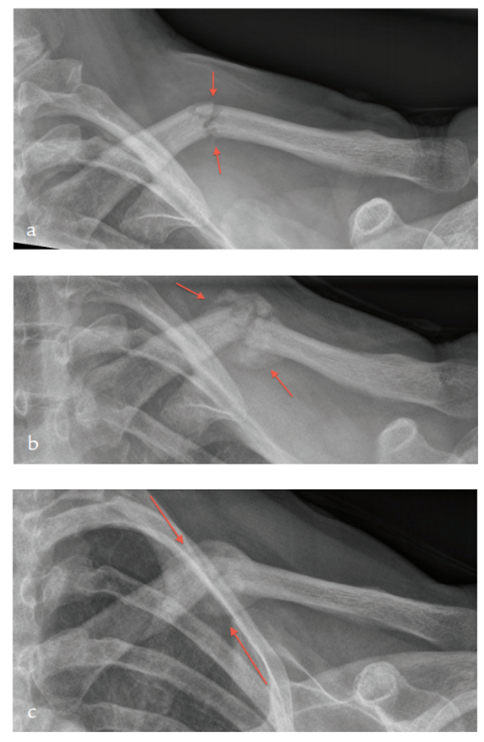

紊乱性纤维化或纤维性瘢痕的临床表现取决于它是发生在局部部位(如瘢痕疙瘩疤痕或手部掌腱膜挛缩症)、影响整个器官(如肝硬化、慢性肾损害或肺间质性疾病)还是全身(如系统性硬化症)。这种影响通常是永久性的,导致相关组织的功能受损。在某些情况下,如特发性肺纤维化(图4),致残性疤痕组织在没有明显炎症的情况下发展。

图4 特发性肺纤维化(IPF)——早期和晚期,自身免疫性疾病的一个例子